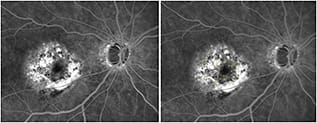

Figure 1. A Navilas treatment plan (left) based on fluorescein angiogram of an eye with diabetic retinopathy and macular edema showing numerous microaneurysms and both focal and diffuse dye leakage. The large yellow circle represents the “no treatment zone,” and the small yellow circles are target laser spots. The retinal thickness map (right) from an OCT scan imported into the Navilas system, overlaid on the FA image, and aligned on the foveal center of the same eye. False color (red) shows retinal thickening.

Figure 2. A Navilas treatment plan (left) based on fluorescein angiogram of an eye with diabetic retinopathy that had been treated previously and that shows residual dye leakage. The large yellow circle represents the “no treatment zone,” and the small yellow circles are target laser spots. The retinal thickness map (right) from an OCT scan imported into the Navilas system, overlaid on the FA image, rotated, and aligned on the foveal center of the same eye. False color (red) shows retinal thickening.